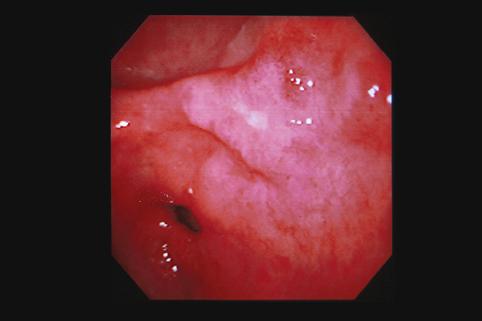

clasificación del pacienteTumor Epitelial Maligno/Adenocarcinoma

parte(separada por órganos)estómago(región)/antro

método de exámenEndoscopia

clasificación ectoscópica de tumoresTipo 0(tipo superficial)/Tipo IIc(IIc)

diámetro mayor del tumor15 - 19

grado de penetraciónm